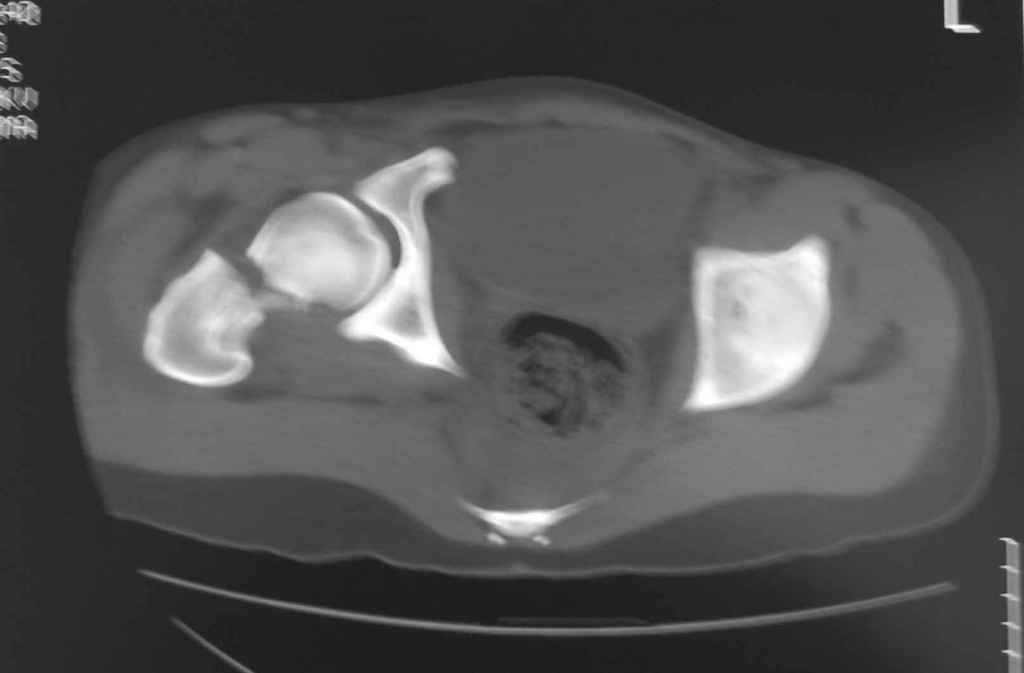

Ребенок 13 лет Перелом костей таза.

Уважаемые коллеги, в нашу клинику поступил ребенок 13 лет; травма четыре дня назад(падение с 5-го этажа). Помогите определиться с дальнейшей тактикой.